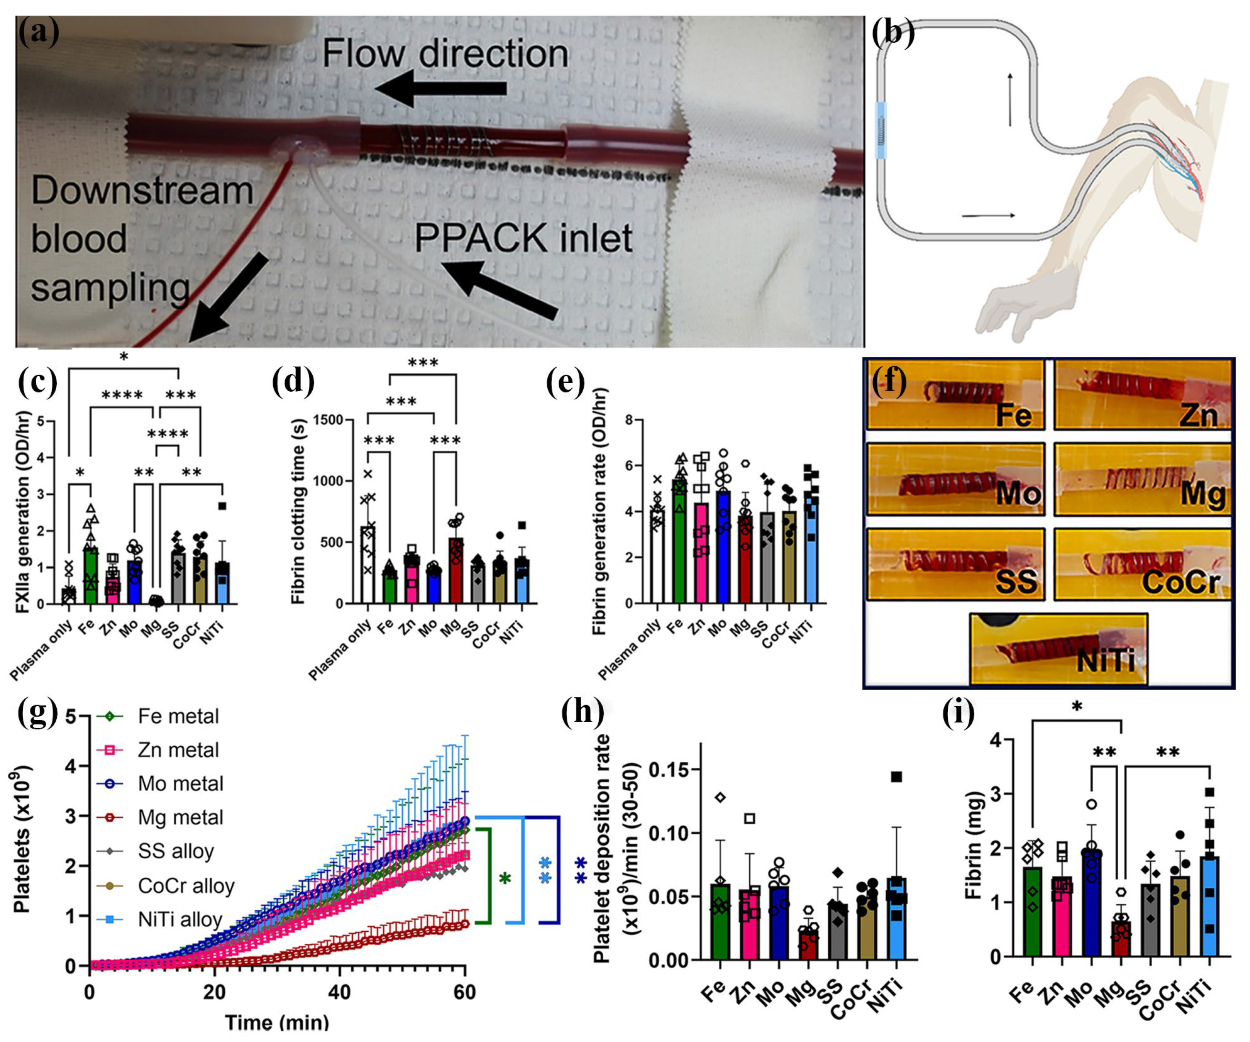

3.5. Cardiovascular Stent

- Anderson, D.E.J.; Le, H.H.; Vu, H.; Johnson, J.; Aslan, J.E.; Goldman, J.; Hinds, M.T. Thrombogenicity of biodegradable metals. Bioact. Mater. 2024, 38, 411–421. [Google Scholar]